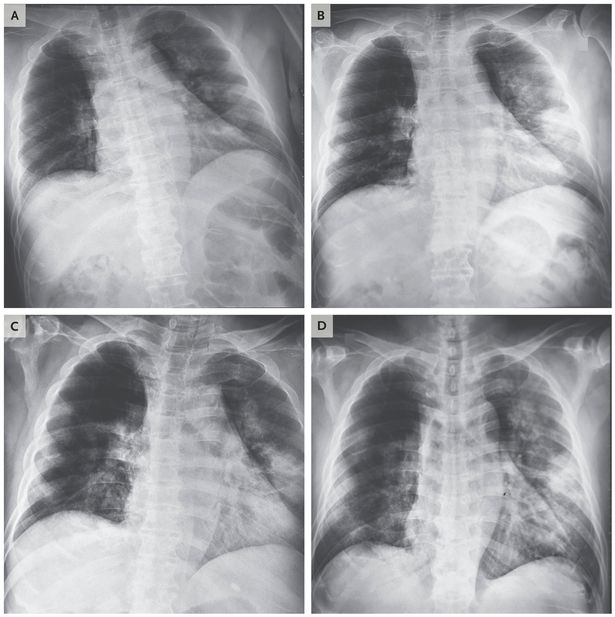

شبكة عصبونية تساعد في كشف الإصابة بكوفيد 19 في صور الأشعة السينية للصدر إم آي تي تكنولوجي ريفيو

الأشعة السينية تكشف حجم الأضرار التي يسببها فيروس كورونا في الرئة صور اليوم السابع

بالصور هكذا يبدو فيروس كورونا في رئتي المصاب الحرة

صور أشعة تكشف ما يفعله كورونا الجديد برئة ضحاياه

صور أشعة مقطعية تكشف كيف يدمر كورونا رئتي الضحايا

Pneumonia Radiology Reference Article Radiopaedia Org